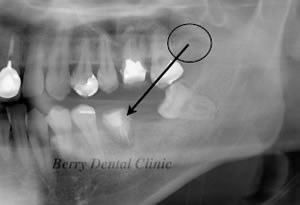

黒色の丸印から1の親知らずが移植されました。

今度は丸印の部分の下の親知らずをすぐ前の位置に移植しました。